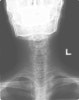

- X-ray

① 추체의 음영 감소, 척추 주위 연부조직의 음영 증가

② 골단판의 불규칙성, 추간판 간격의 협소

③ 후기 후만증, 측만증 등의 척추 기형

X-ray : 척추 결핵(Spinal tuberculosis)